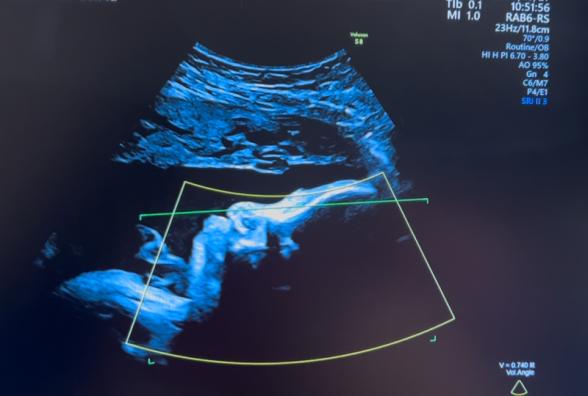

妊婦健診で4Dのエコー写真を撮って頂けるのですが、

顔の特徴がダウン症の特徴と同じのような感じがして

不安です。鼻は低いし目がつり目?のような浮腫んでるような…。

※写真は28週、35週、32週の順です。

実際にエコー写真でダウン症顔貌かの判断は、できないかなと思います。私からみて、エコーでみる赤ちゃんの顔としては、特徴的な顔貌の印象はないです。

エコー画像は、実際に見る感じとは、少し違う感じに見えるかなと思います。